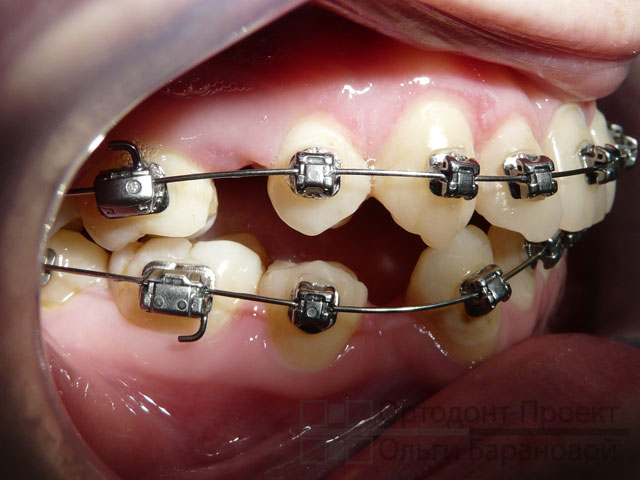

Металлические брекеты Damon на зубах:

Через 2,5 месяца после установки брекетов на зубы заметно сократились промежутки от удаленных зубов:

Через 4 месяца после начала лечения форма зубных рядов стала намного ровнее, остаются еще промежутки от удаленных зубов:

Через 8 месяцев после начала лечения брекетами Damon:

Для создания правильных контактов между зубами, ортодонт назначила ношение эластичных тяг. Ортоэластики носят весь день и в течение ночи, снимая их только для проведения гигиены. Для окончательного закрытия промежутков от удаленных зубов брекет-система дополнена специальными закрывающими пружинами.

Вид зубов через 1 год и 4 месяца от начала лечения:

Вопреки довольно сильному заблуждению о том, что на брекет-системе Damon всё и всегда лечится без удаления, эта работа показывает, что ВОВСЕ НЕТ. И Доктор Дуайт Дэймон сам никогда такого не провозглашал. Всё надо делать по показаниям. В данной работе О.А. Баранова предложила использовать брекеты Damon с удалением зубов. Самолигирующиеся брекеты Damon легко скользят по дуге, оказывая на зубы постоянные небольшие силы воздействия, и передвигая зубы в новое положение быстрее других брекетов. В данной ситуации механизм пассивного самолигирования был использован для того, чтобы быстрее закрыть промежутки от удаленных зубов.